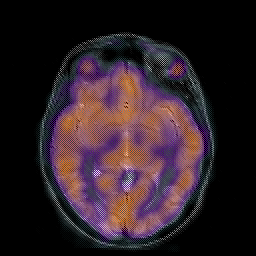

Hypertensive Encephalopathy, overlay -- Slice #11

[Home][Help][Clinical] Slice 11